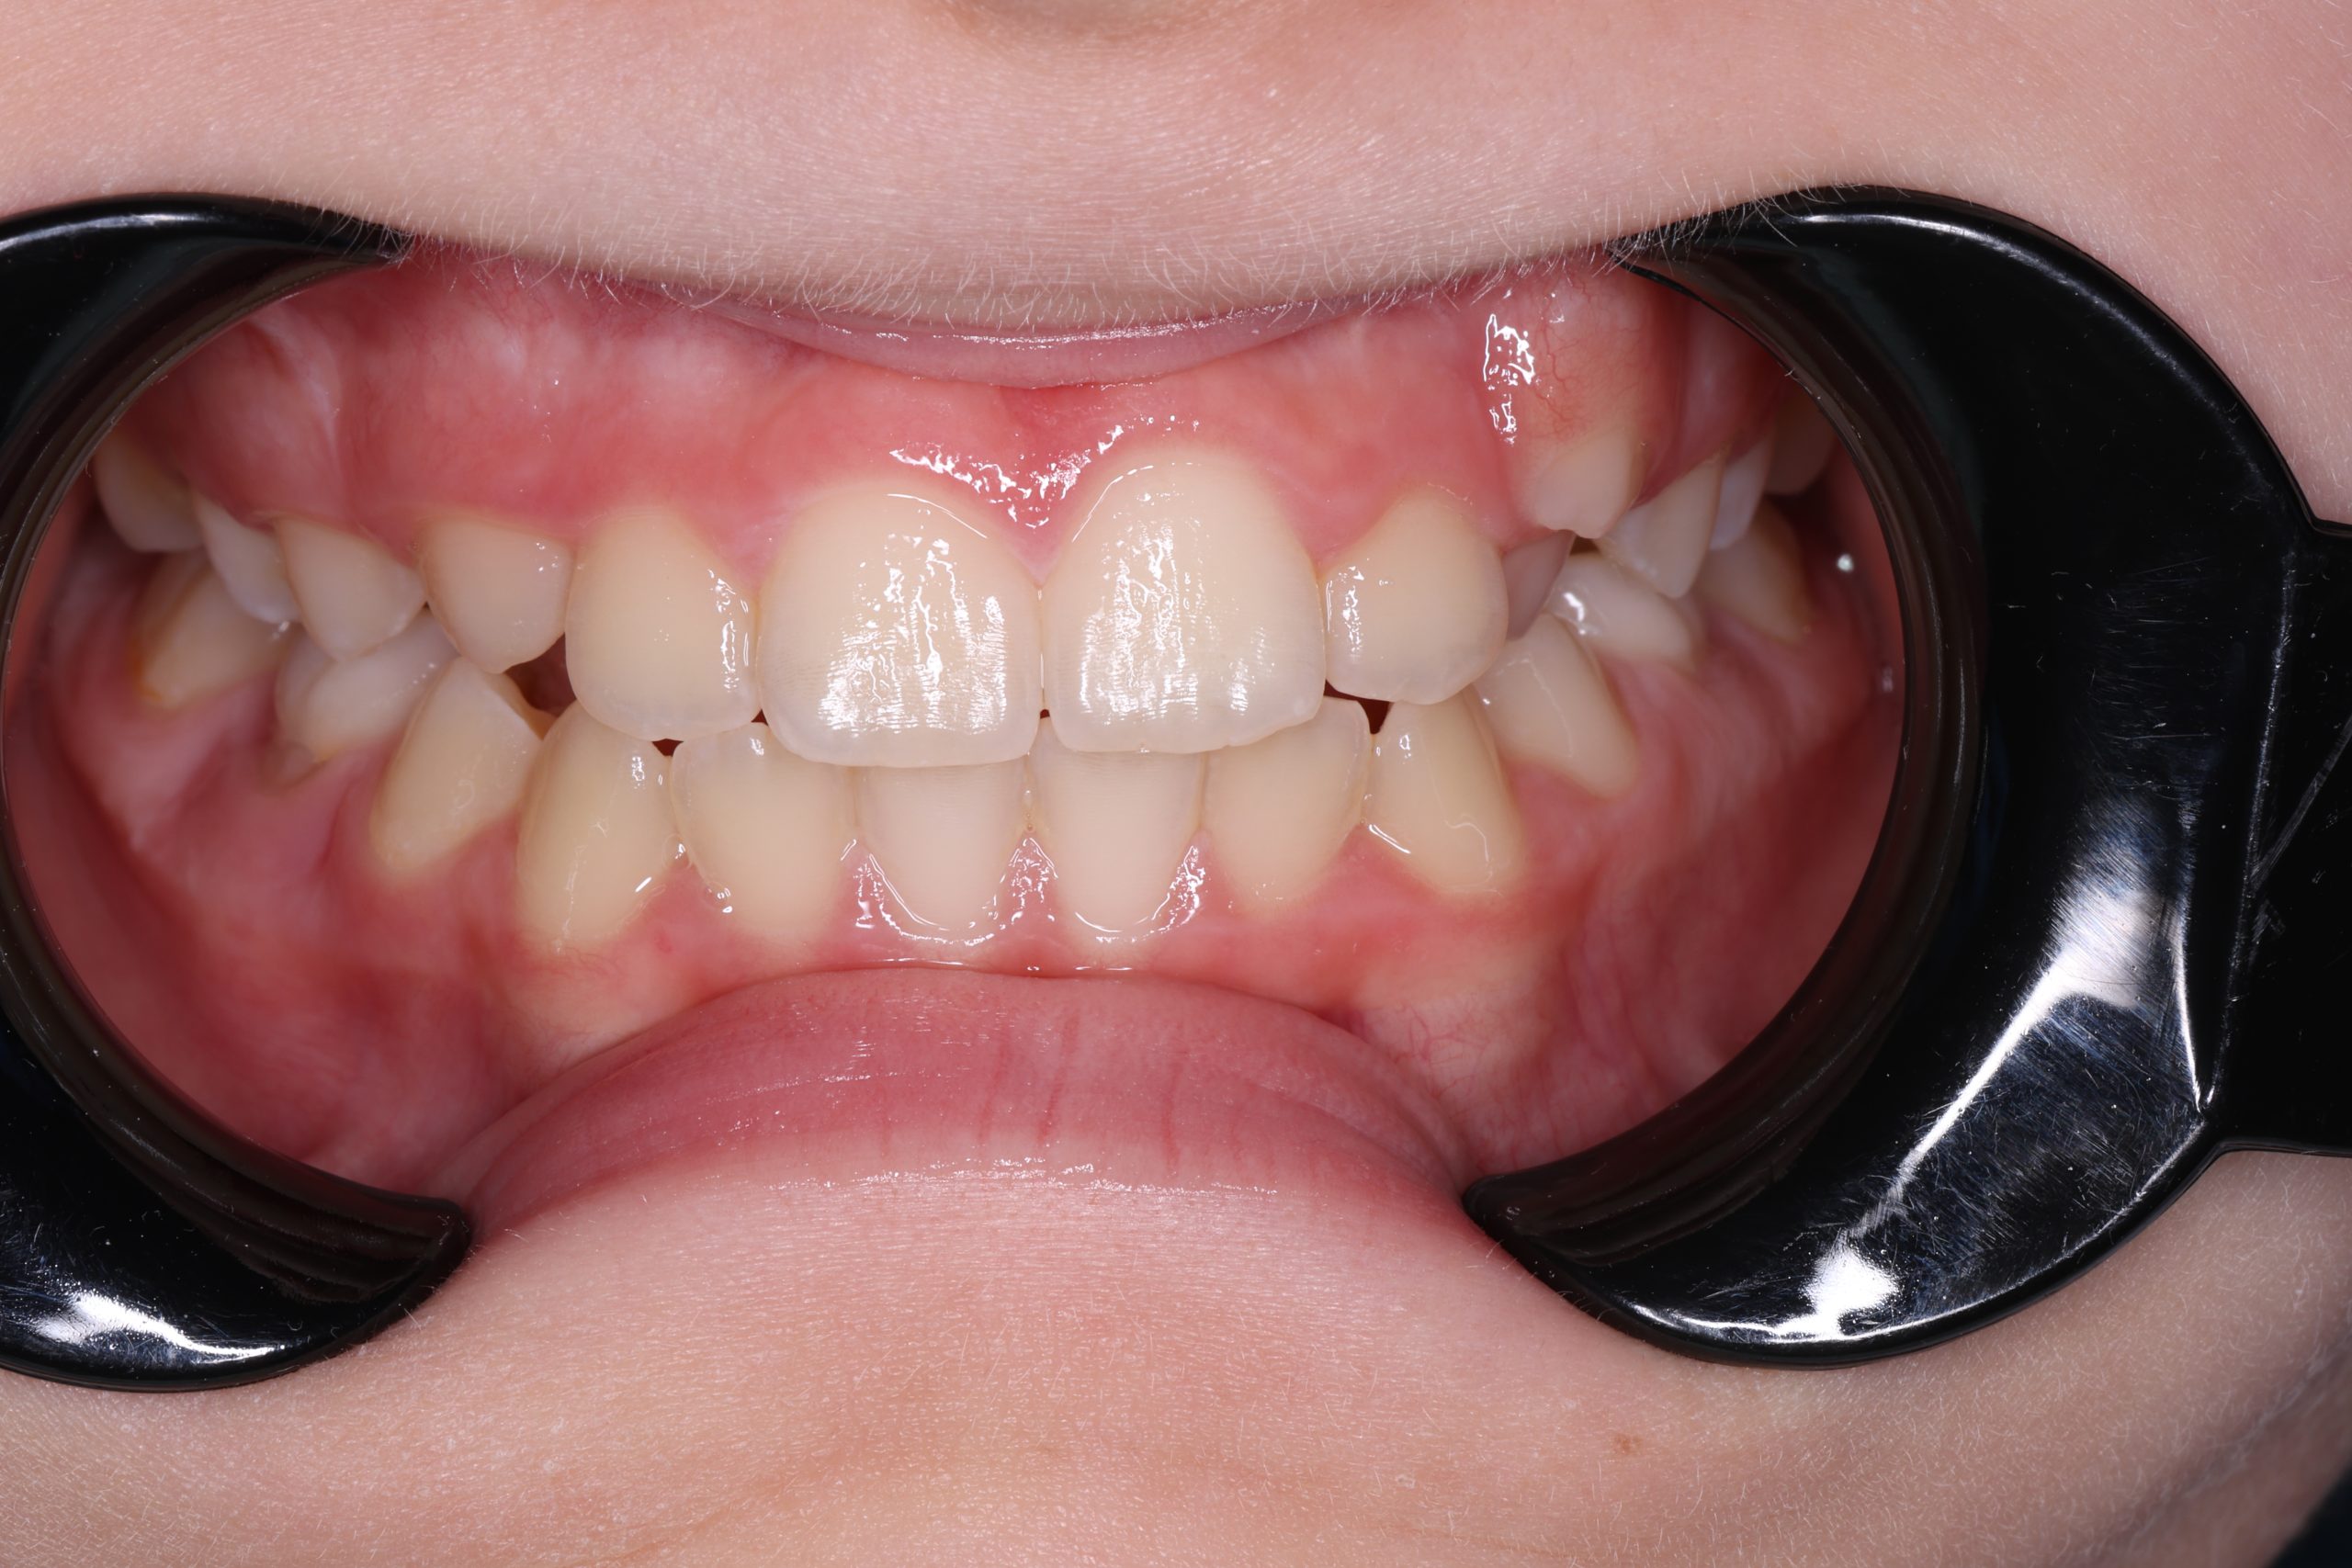

Any tartar is removed gently and painlessly. - Final Check-Up + Fluoride Protection

We ensure the teeth are clean and free from early caries (even in the spot stage), then apply fluoride varnish to protect and strengthen enamel. - Personalized Recall Plan